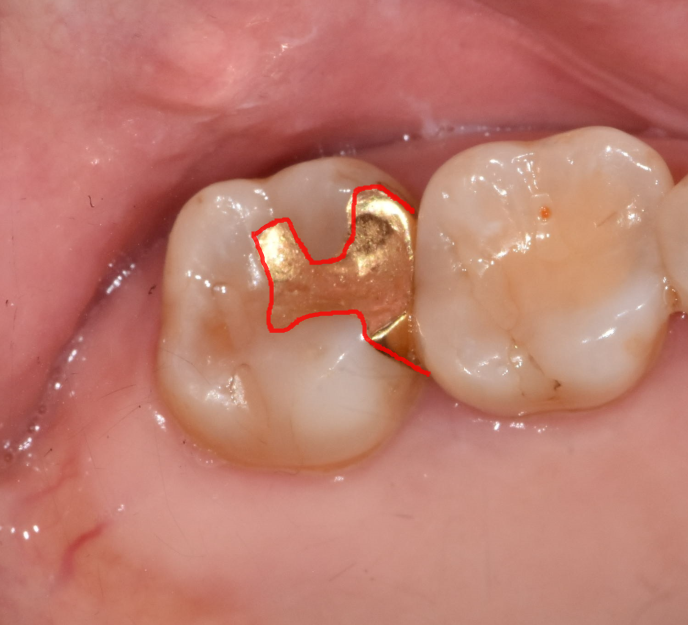

충치를 제거하고 "인레이" 치료를 해야하는데요.

230708

이렇게 조각 모양으로 생긴 치료가 "인레이"입니다!!

(주로 치아 사이 충치를 치료할 때 사용됩니다.)